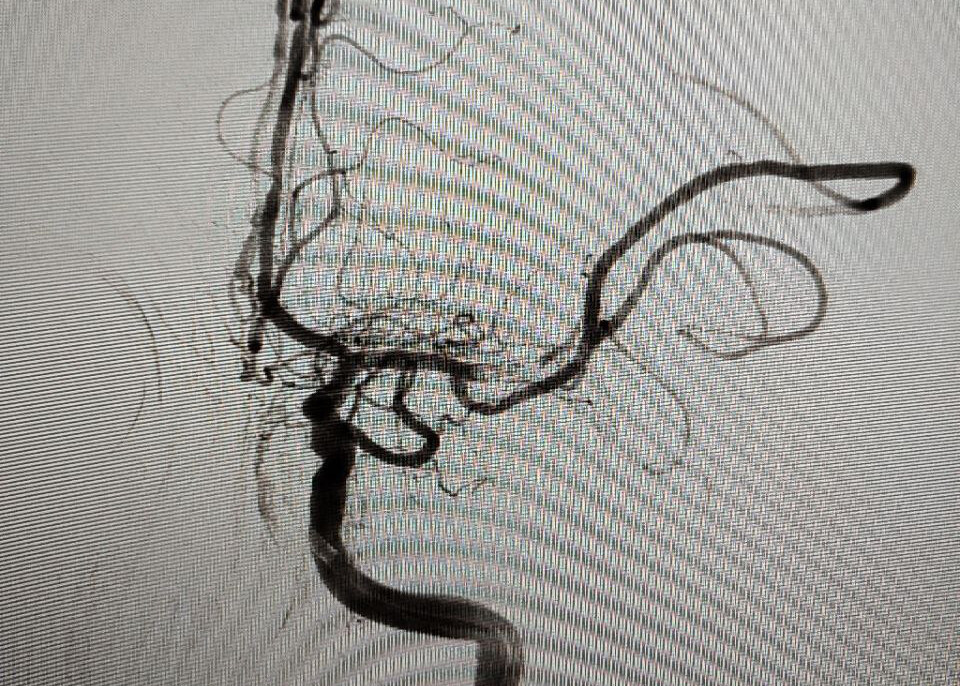

Врачи Луганской республиканской клинической больницы (ЛРКБ)  провели первые пять операций по эмболизации аневризмы головного мозга. Об этом в своем Telegram- канале сообщила министр здравоохранения ЛНР Наталия Пащенко.

"Впервые в ЛНР для лечения этой патологии применяется хирургический и нехирургический метод, успешно проведены 13 тромболитических терапий, пять успешных операций - эндоваскулярная тромбэкстракция, которые относятся к высокотехнологичным операциям. И все они выполнены нашими подготовленными специалистами", - проинформировала министр.

Она пояснила, что в процессе операции через бедренную артерию пациенту вводится микрокатетер, который далее проводится под рентгеном до сосудов головного мозга. По микрокатетеру заводится внутрисосудистый стент-ретривер - специальная ловушка для тромба. Стент-ретривер раскрывается на уровне тромба, оценивается захват тромба стентом, далее стент-ретривер удаляется в раскрытом виде. Таким образом в процессе операции артерия освобождается от тромба, восстанавливается кровообращение, препятствуя развитию инсульта.